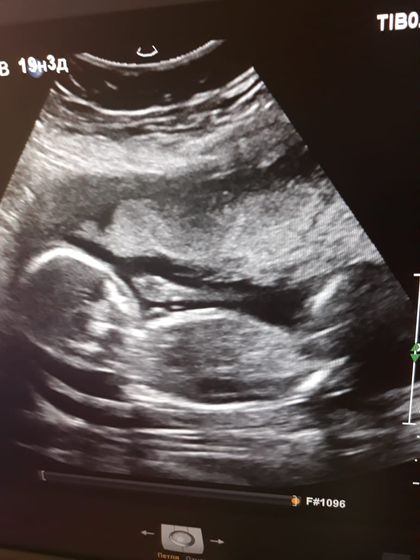

Сходили с мужем на второй скрининг, пустили его тоже в кабинет, но быстренько показали детку и выгнали в коридор ждать))) Слава Богу, все в порядке! Подтвердили нам девочку, ну я, собственно, и не удивлена=) С Тимкой чувствовала, что мальчик, и сейчас с Авелинкой чувствую, что девочка, с первых дней беременности)Не знаю, как так вообще, как говорится, невероятно, но факт=) Пост в основном для себя на память)

Спасибо!=)Ой, как я вас понимаю))))Я тоже дождаться не могла! Все усугублялось тем, что до 19ой недели я чувствовала шевеления, а в 19 резко перестала! Перестала после истерики своей и перепугалась жутко, думала, не дай Бог с ней что-то случилось… На УЗИ успокоилась=) А сразу после УЗИ начала опять ее чувствовать=)Насчет девочки-дай Бог вам ее, если так хочется=)))А вообще конечно пол совсем не важен, главное, чтобы здоровенький был=)